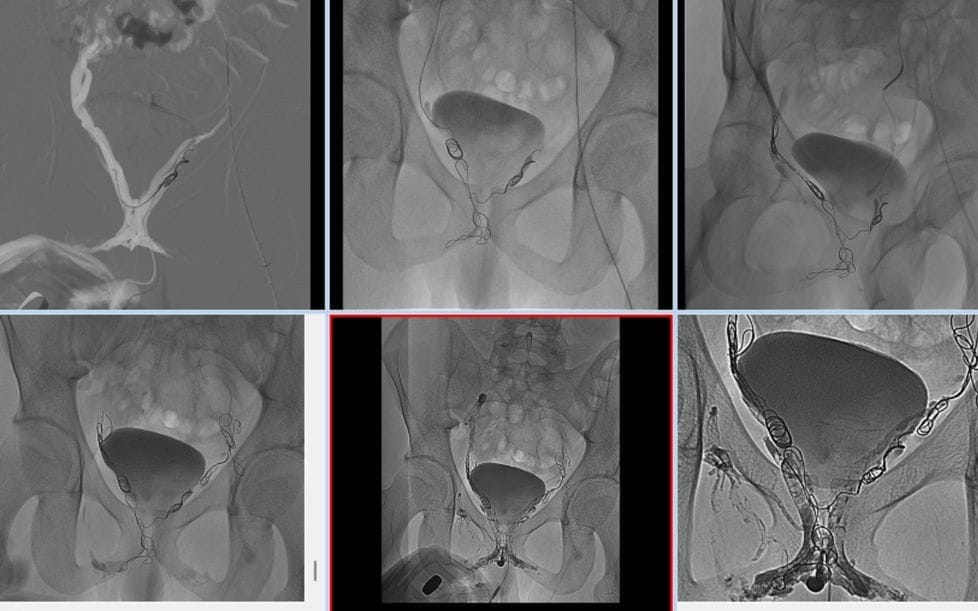

- imagine de închidere a leak-ului venos penian

Metodele endovasculare de tratament ale disfuncției erectile veno-genice sunt evaluate din punct de vedere tehnic și clinic. Rata de succes tehnică este ridicată. Totuși, ratele de succes clinic sunt mai variate și, în general, au fost înregistrate la 59,5%. Aceste valori variază între 21,9% și 100%.

Tratamentul leak-ului venos penian prin abordare anterogradă prin vena dorsală profundă (din vena colectoare la rădăcina penisului)

În tratamentul endovascular al disfuncției erectile, abordarea anterogradă este considerată o metodă sigură și eficientă. Procedura se realizează cu atenție în sala de angiografie. Pacientul este așezat pe spate și pregătit corespunzător, fiind acoperit adecvat. Se administrează lidocain pentru anestezie locală. Pașii de bază ai procedurii sunt următorii:

- Vena dorsală profundă este identificată folosind ultrasunetele.

- Vena este punctată folosind un set de micro-punctare.

- Pentru cateterizare se utilizează un cateter diagnostic și un glidewire sub fluoroscopie.

Urmărește un venogram diagnostic, iar pentru embolizare se preferă materiale speciale. Materialele utilizate în timpul embolizării sunt:

- O combinație de N-butil-2-sianoacrilat și ulei etiodizat,

- Manoevrele Valsalva și controlul fluoroscopic continuu,

- Proiecție oblică, pentru a preveni embolizarea țintită incorect,

- Cateterul este spălat cu o soluție de glucoză de 5%,

- Coil-uri fibrozate pentru venele cu flux rapid.

În perioada perioperatorie se poate administra sedare și analgezice. Acest proces este critic pentru confortul pacientului și succesul procedurii.

Abordare venoză retrogradă transfemorală prin embolizare transcateter

Una dintre metodele noi și eficiente în tratamentul disfuncției erectile este abordarea venoză retrogradă transfemorală prin embolizare transcateter. Această tehnică se realizează prin venele iliace interne și vizează embolizarea, în special, a venelor pudendale interne și a plexului venos periprostatic. Este o opțiune minim invazivă pentru pacienți și nu necesită anestezie generală. Materialele utilizate în timpul procedurii sunt: